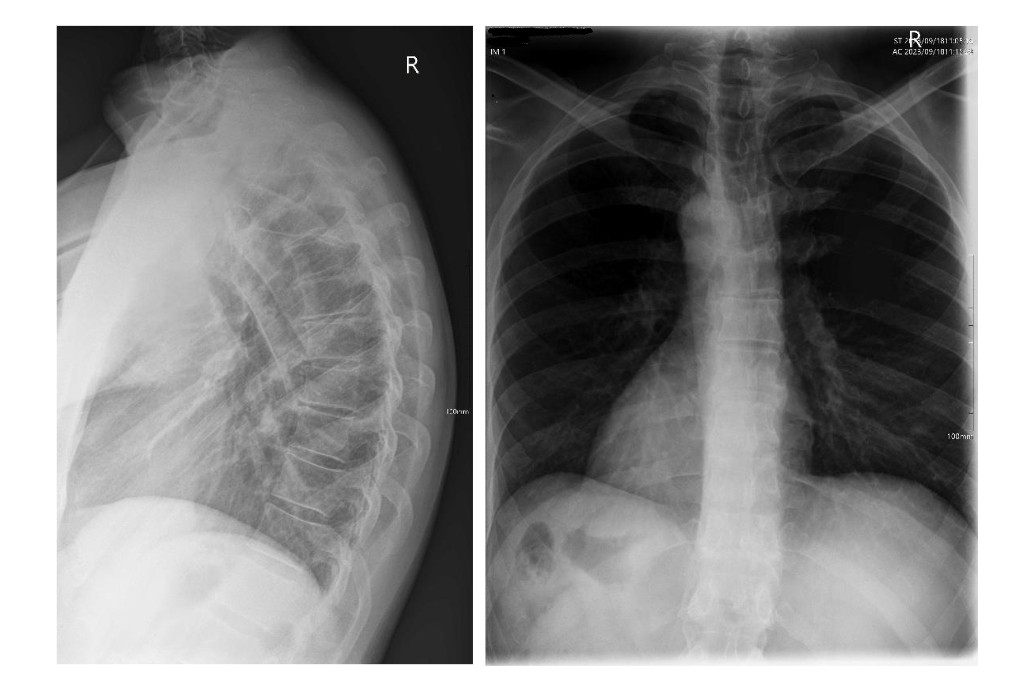

Fig. 2 – Thoracic lateral and PA x-rays showing a thoracic hyperkyphosis with Sorenson's signs.

Biomechanical radiographic analysis of the thoracic spine revealed an excessive thoracic kyphosis of 63.39° as measured from the T1 superior endplate to the T12 inferior endplate, with the apex occurring at T7/8. Vertebral wedging of greater than occurred at T7, T8 and T9. Other radiographic features of note were; reduced disc spaces at T5/6, T6/7 and T8/9; degenerative changes at the superior endplates of T4, T6, T7 and T9; and degenerative changes at the inferior endplates of T6, T7 and T8. Other minor changes noted were a mild lateral curvature of the thoracic spine, measured at a Cobb angle of .